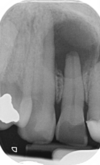

47

what is shown on this picture?

periacpical granuloma